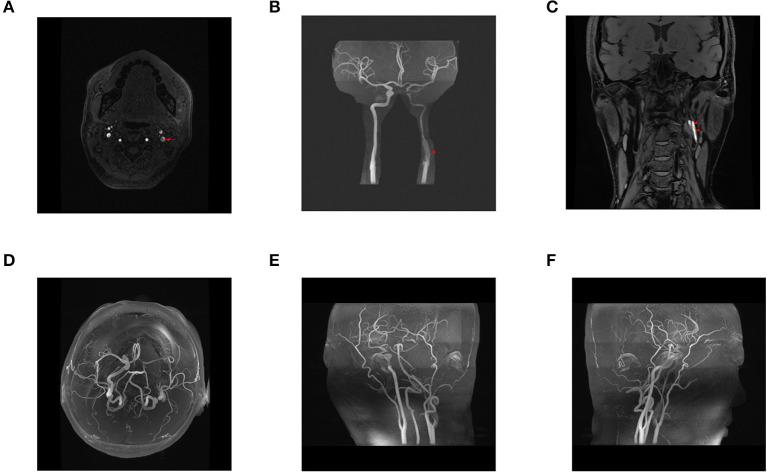

A 41-year-old woman developed headache and clinical manifestations of cerebral infarction after 7D HIFU, aimed at removing neckline. Head and neck magnetic resonance angiography (MRA) and computed tomography angiogram (CTA) revealed severe stenosis and dissection of the left internal carotid artery. Neither the patient's history nor the physical examination showed any special indicators. After resection of the left carotid artery dissection, autologous great saphenous vein interposition grafting, and simple mastoidectomy, the patient underwent head and neck MRA, which revealed recanalization of the left internal carotid artery.

一名41岁女性在接受旨在去除颈部皱纹的7D HIFU治疗后出现头痛及脑梗死临床表现。头颈部磁共振血管造影(MRA)和计算机断层血管造影(CTA)显示左颈内动脉严重狭窄及夹层形成。患者病史及体格检查均未显示任何特殊指征。在切除左颈动脉夹层、自体大隐静脉搭桥及单纯乳突切除术后,患者接受头颈部MRA检查,显示左颈内动脉再通。